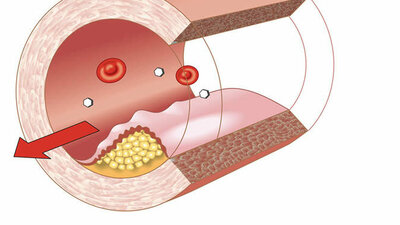

Die Aortendissektion ist eine der häufigsten Schäden, die in der Aorta auftreten. Sie ist potentiell lebensbedrohlich: Es handelt sich um einen Riss der inneren Schicht, der dazu führt, dass Blut in die Gefäßwand eindringt, diese dadurch aufdehnt und einreißen kann.

Am Anfang wurden zwei Typen von Aortendissektionen unterschieden: Typ A umfasst die Aorta ascendens, vereinfacht gesagt den vom Herz aus aufsteigenden Teil der Aorta. Typ B umfasst die Aorta descendens, den absteigenden Teil. Der dazwischen gelegene Aortenbogen war in dieser Klassifikation noch nicht berücksichtigt. Deswegen kam der Begriff der Non-A-non-B-Dissektion dazu, um diese Komponente abzubilden. Um Aortendissektionen heute zu behandeln, braucht es einen umfassenderen Blick, die Aortenmedizin.